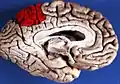

![]() Sagittal MRI slice with the precuneus shown in red. (Anterior to the left.) | |